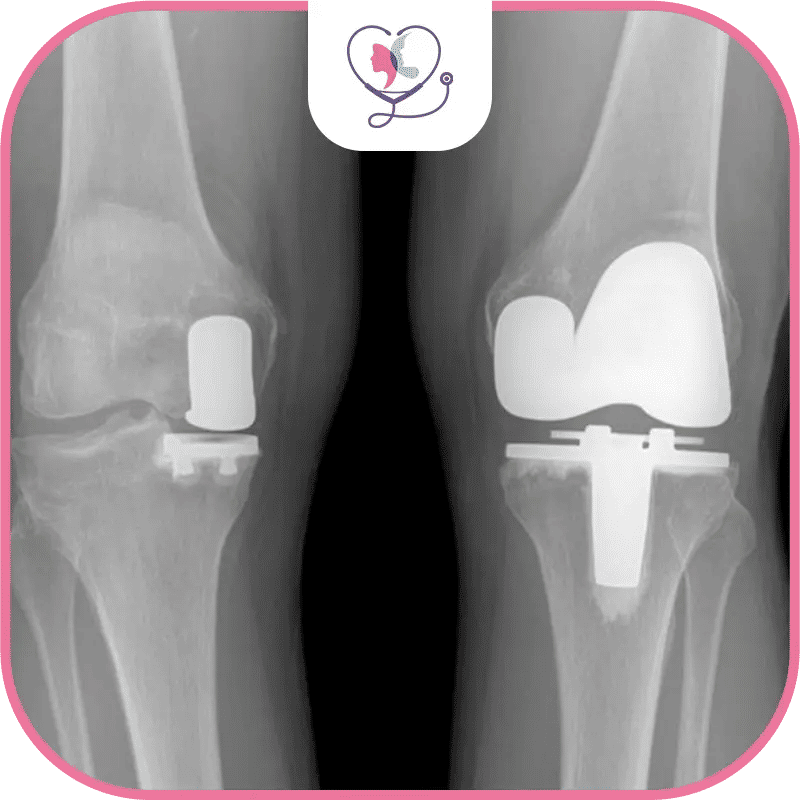

Chirurgie bilatérale du genou

La chirurgie bilatérale du genou (CBG), ou chirurgie double du genou, consiste à réaliser une intervention sur les deux genoux simultanément.

Selon l'AAOS, la CBG peut être avantageuse lorsque les deux genoux sont touchés par l'arthrose. Elle peut réduire les coûts globaux et minimiser le nombre de séjours à l'hôpital.